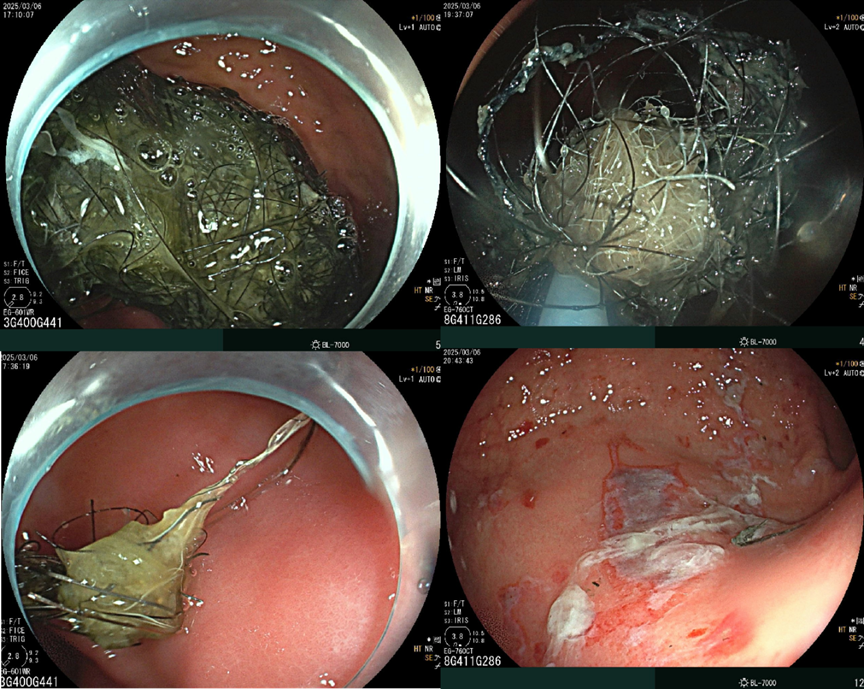

“毛石怪兽”沉胃中

内镜巧取一扫空

紧急安排的胃镜检查让所有人倒吸一口凉气 —— 胃里竟盘踞着一个拳头大小的 "毛石怪兽"。这不是普通的“石头”,而是由无数根头发与胃内容物编织而成的黑色硬块。此时,在胃镜下观察到部分胃和十二指肠黏膜出现了溃疡,若持续不处理可能会引发出血,导致病情恶化。

无需开刀,内镜外科主任郭学峰主任医师团队决定胃镜下取出毛石。一整块取出肯定不现实,于是,团队先行电切割,分小块后再取出体外。这是胃镜下治疗的常规操作,但是要保证取出时不造成二次伤害,需小心谨慎,且毛石结构紧密,操作上很费力,并没有想象中那般轻松。由郭学峰指导,钟清华副主任医师及林德政主治医师共同操作,经过4个多小时努力,“毛石怪兽”被全部取出。